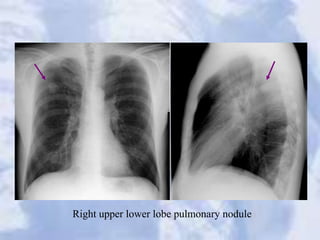

Case 17

Right upper lower lobe pulmonary nodule

Right upper lowerlobe pulmonary nodule